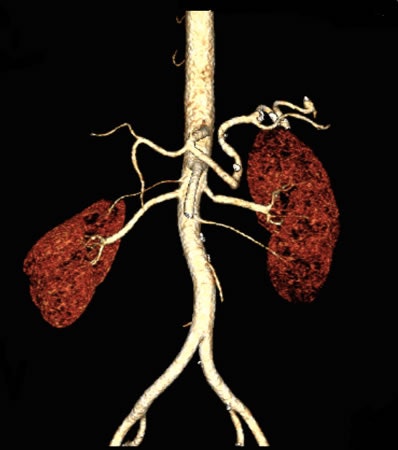

The investigators from Northwestern University examined 20 patients referred for abdominopelvic CTA using a novel protocol that substantially reduced both radiation dose and contrast. Even with a dose as low as 3 mSv of radiation and 15 mL of iodinated contrast, the results showed no reduction in objective or subjective image quality using the technique.

"We showed that abdominal CT using an ultralow-dose contrast protocol is clinically and technically feasible, and we can achieve good image quality and homogeneous attenuation across vascular levels," said Dr. Faezeh Sodagari, who received an RSNA Student Travel Stipend Award for the CTA abstract.

The investigators assessed intravascular contrast attenuation at the suprarenal aorta, infrarenal aorta, and right common iliac artery. They determined image noise, contrast-to-noise (C/N) ratio, and signal-to-noise (S/N) ratio. Sodagari and colleagues also extracted CT dose index volume (CTDIvol) from dose reports, and used repeated-measures analysis of variances for data analysis.

The mean CTDIvol was 3.8 ± 1.1, the mean C/N ratio was 9.2 ± 4.9, and the mean S/N ratio was 9.9 ± 4.1. Attenuation was homogeneous across vascular levels.

Regarding subjective image quality, 45% of the images were rated acceptable, 30% were good, and 25% were excellent, Sodagari said. Objective image quality parameters showed good C/N and S/N ratios, with relatively low noise levels considering the mean effective dose. Median CTDIvol was 3.4 at 80 kV and 3.6 at 90 kV.

Ultralow-dose contrast CTA with low radiation dose is both technically and clinically feasible, producing high image quality and homogeneous attenuation, Sodagari concluded.

The study shows the potential for reducing the contrast dose to as low as 15 mL for high-pitch abdominopelvic CT angiography at 80 kV. This may have clinical implications in abdominopelvic CT angiography, particularly in patients with renal impairment.